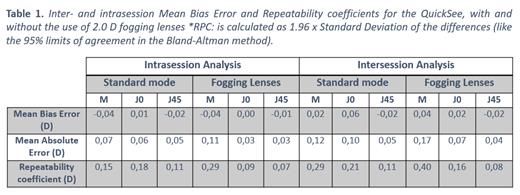

PurposeHigh repeatability portable autorefractors may enable effective deploy of global-health initiatives to mitigate uncorrected refractive error worldwide. For example, in studies to evaluate the effectiveness of different measures, repeatability has a direct impact on the statistical power and sample size required, while in screening applications, contributes to increased sensitivity and specificity. This work presents a preliminary assessment of the inter- and intrasession repeatability of an affordable autorefractor (QuickSee, PlenOptika Inc) under two separate measurement conditions, with and without fogging lenses. Methods6 volunteers (29,8 ± 8,1 years old) were measured at 2 different sessions spaced 1-week. Each subject was tested 6 times per session with the QuickSee, 3 times in standard mode and 3 using a modified version of the device eyecup to allow over-refraction through fogging lenses (+2.0 D). Intersession measurements were spaced 5 minutes apart and the complete alignment procedure was repeated for each measurement. After converting autorefractor readings into power vectors (M, J0, J45), repeatability was evaluated using the Bland-Altman method to compare differences between all possible combinations from each subject (inter- and intrasession). Repeatability coefficients (RPC), estimated as the 95% limits of agreement, and the mean absolute errors were also evaluated. In all cases, only results for the right eyes were analyzed. ResultsParticipants had an average Spherical Equivalent (SE) refraction of -0.75 ± 2.06 D, (Min -5.11 D, Max 0.175 D). A total of 36 samples per dataset were obtained for the intrasession analysis while 54 samples per dataset were used in the intersession comparison. In all cases the mean difference was practically 0 indicating no bias for any of the vector components. SE RPCs for intrasession test were 0.15 D in standard mode and 0.29 D with the fogging lenses. Intersession RPCs were 0.29 D and 0.4 D without and with the fogging lenses, respectively. Detailed results for all vector components are shown in Table 1. ConclusionsThis preliminary analysis shows that the device can provide excellent RPCs in standard mode, which decrease moderately with the use of the fogging lenses. Further work exploring improvements in the eyecup design and measurement averaging techniques may further enhance the RPC values in over-refraction mode. |